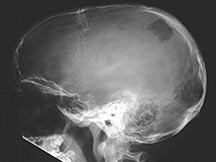

- Any bone but 90% have skull involvement

- Skull